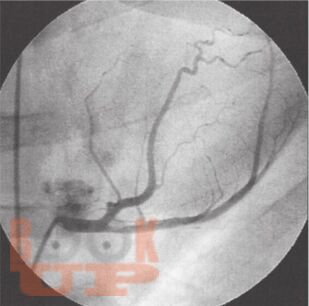

В книге всемирно известных авторов детально представлены вопросы применения электрокардиографии при инфаркте миокарда с подъемом ST. Предложенный авторами революционный подход к интерпретации стандартной ЭКГ в 12 отведениях позволяет не только констатировать наличие инфаркта и определить его локализацию, но с большой точностью установить, окклюзия какой коронарной артерии и на каком уровне произошла и какие сегменты миокарда оказались вовлечены в патологический процесс. Это существенно расширяет потенциал ЭКГ в современных условиях широкого применения методов интервенционной кардиологии и кардиохирургии, а также увеличивает прогностические возможности электрокардиографии при остром инфаркте миокарда.